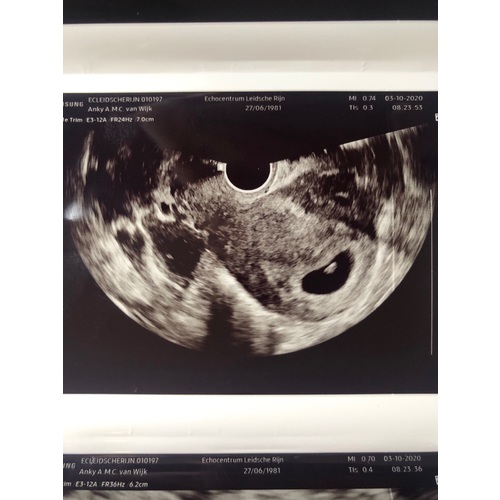

Bedankt voor je reactie,, nee het zat echt aan de bovenkant van me baarmoeder naast de baby maar heb dinsdag me intake via de telefoon dan vraag ik het nog even. Hopelijk heb ik dan wel de zelfde vrouw want bij onze verloskundige praktijk zitten 4 verschillende dames die echos doen hahaha 😅

Bij mij zagen ze ook meerdere holtes, veel tweelingen (alleen van moeders kant tellen mee!) in de familie, uiteindelijk steeds maar een!